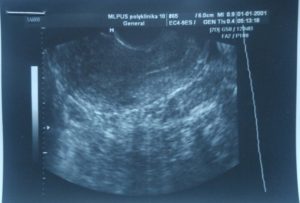

УЗИ диагностика беременности предполагает обнаружение плодного яйца в полости матки. В норме на 5-6-й неделе оно имеет вид каплевидного или округлого эхонегативного образования, окруженного по всей периферии гиперэхогенным валиком, диаметром в 6 мм. При этом на ранних сроках эмбрион ежедневно в среднем увеличивается на 1 миллиметр.

К 6-7-й неделе плодное яйцо практически полностью заполняет маточную полость и при продольном сканировании имеет овальную форму, а при поперечном – округлую.

Также врачу важно найти желточный мешок, который лучше всего визуализируется на 8-й неделе (5 мм) и представлен округлой формой с жидкостным содержимым. Эмбрион же определяется как утолщение его краев, поэтому на мониторе виден «двойной пузырек».